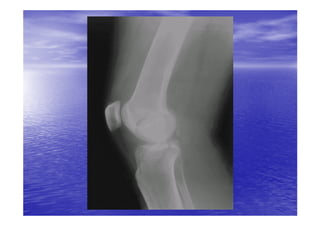

RADIO-

RADIO-ANATOMIE

• Le genou peut être exploré par les incidences

radiologiques suivantes:

– La radiographie standard de genou face/profil

– Arthrographie grâce à l'injection à l'intérieur de la

cavité articulaire du genou d'un produit de contraste

radio-opaque , on peut étudier l’épaisseur des

cartilages articulaires , les ligaments croisés , surtout

les ménisques.

– Arthrographie et scanner.

– IRM.est un excellent moyen d'étudier les ménisques ,

les ligaments , les cavités articulaires et les éléments

squelettiques.